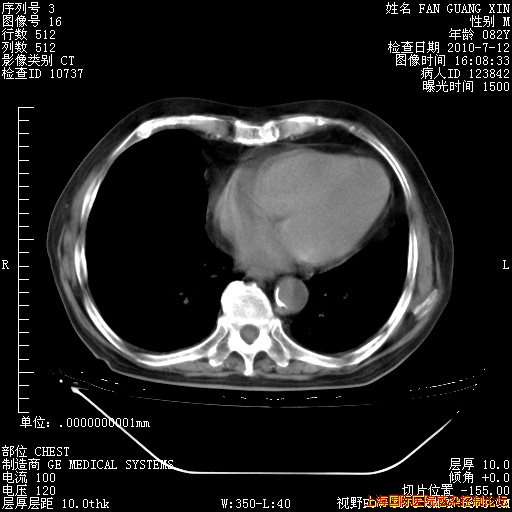

6月12日纵膈窗

今天复查CT

今天CT

整整相隔30天的肺部CT好像有所好转啊。甲强龙减量第3天,需要观察体温。